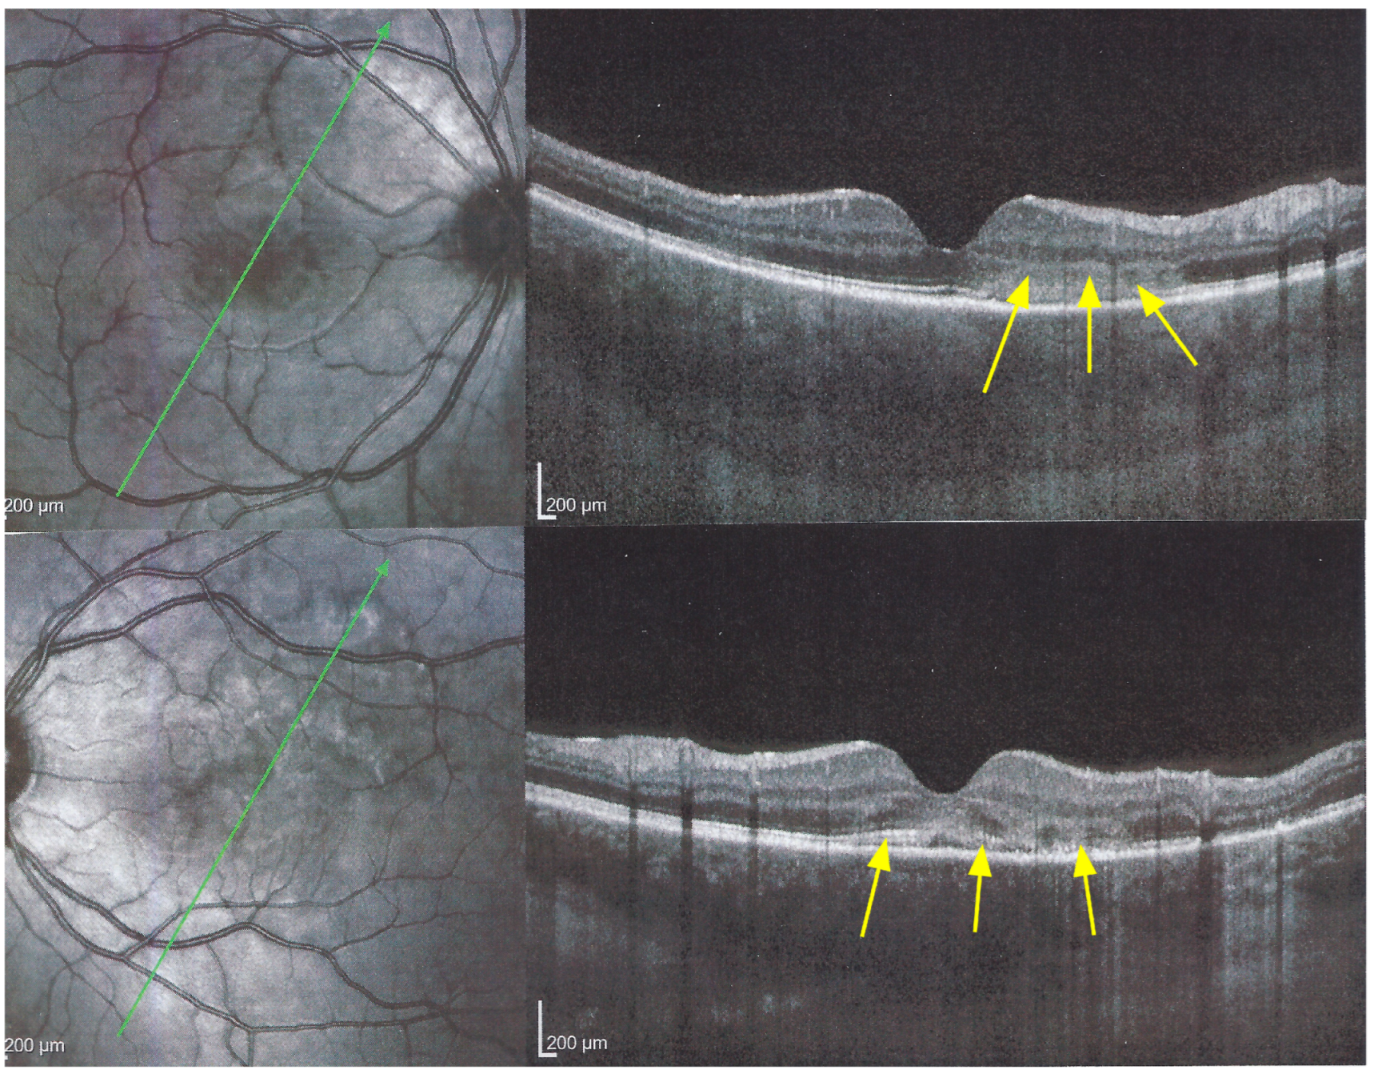

Figure 9. APMPPE/AMIC; SD-OCT in subacute phase OD (top) and OS (bottom) (same patient as Figure 5, Figure 6, Figure 7a and Figure 8). In the subacute phase, SD-OCT shows extended areas of loss of photoreceptor outer segments (arrows) and thickened RPE, hyperautofluorescent on BL-FAF (see Figure 5).

The chorioretinal findings by spectral domain optical coherence tomography (SD-OCT) depend on the degree of involvement and the stage of the disease [5,7,25]. In early-acute disease ischaemia, induced by choriocapillaris non-perfusion, causes thickening of the outer retina including the IS/OS line and beyond (Figure 8). In later stages, SD-OCT can show either simple loss of photoreceptor outer segments, thickened RPE or atrophy with loss of RPE (Figure 9).

SD-OCT findings included thickened hyperreflective areas of the outer retina in the very early disease phase (10/35 eyes) (Figure 8 and Figure 11), photoreceptor outer segment loss and/or ellipsoid zone disruption-RPE alterations (22/35 eyes) (Figure 9), subretinal fluid (serous retinal detachment—SRD) (4/35 eyes), (Figure 14) and atrophy (3/35 eyes) in the late stage of the disease (Figure 15).